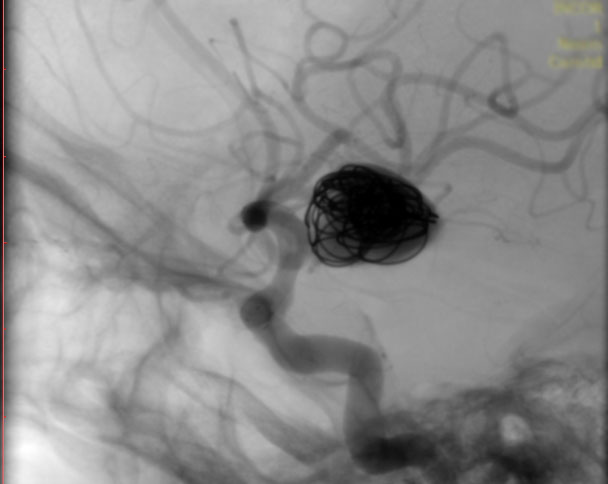

La paciente ingreso al Servicio de Hemodinamia el día martes 11 de febrero con un aneurisma cerebral gigante en la carótida izquierda y se le practicó una embolización; es decir una oclusión por dentro del mismo, donde se colocó un dispositivo denominado coils más un stent diversor de flujo. El procedimiento fue exitoso y contó con la colaboración de médicos neurointervencionistas del Instituto Oulton de la Ciudad de Córdoba.